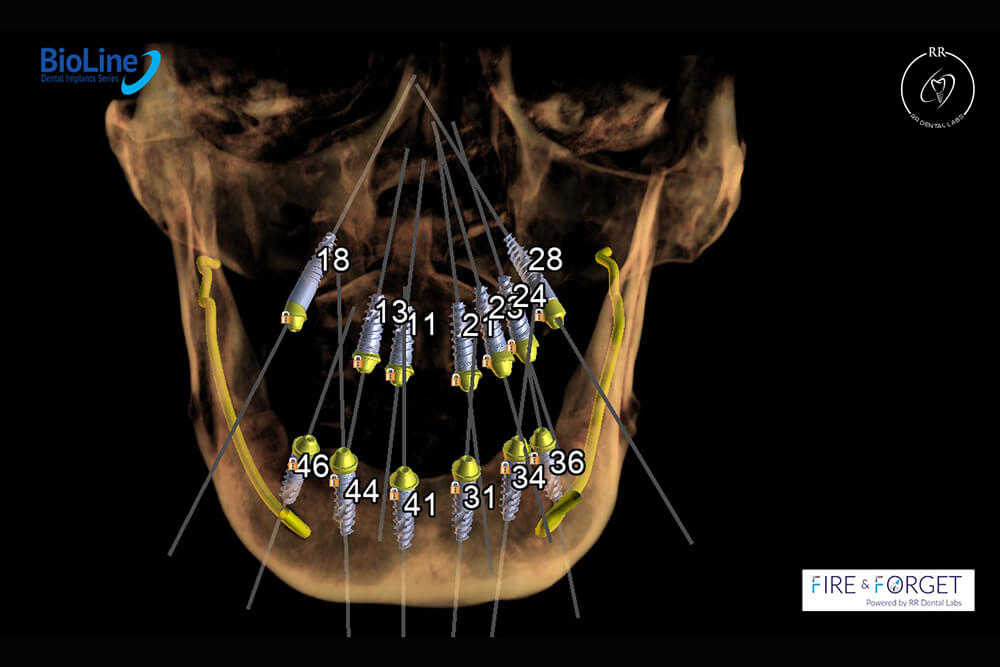

Case 47